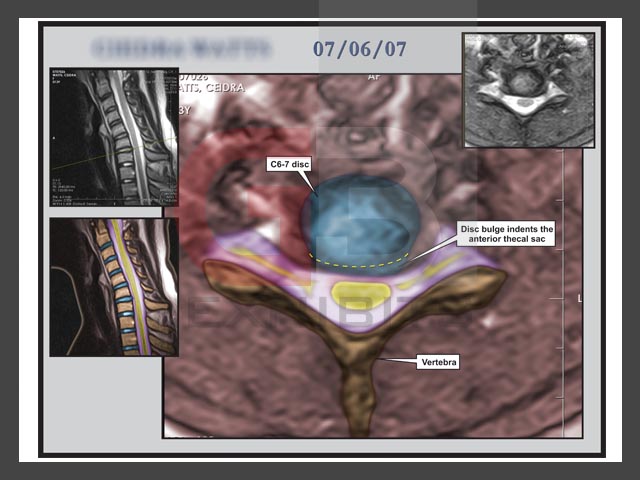

Click to enlarge: Neck Click to enlarge: Neck Click to enlarge: Brain Slice 1